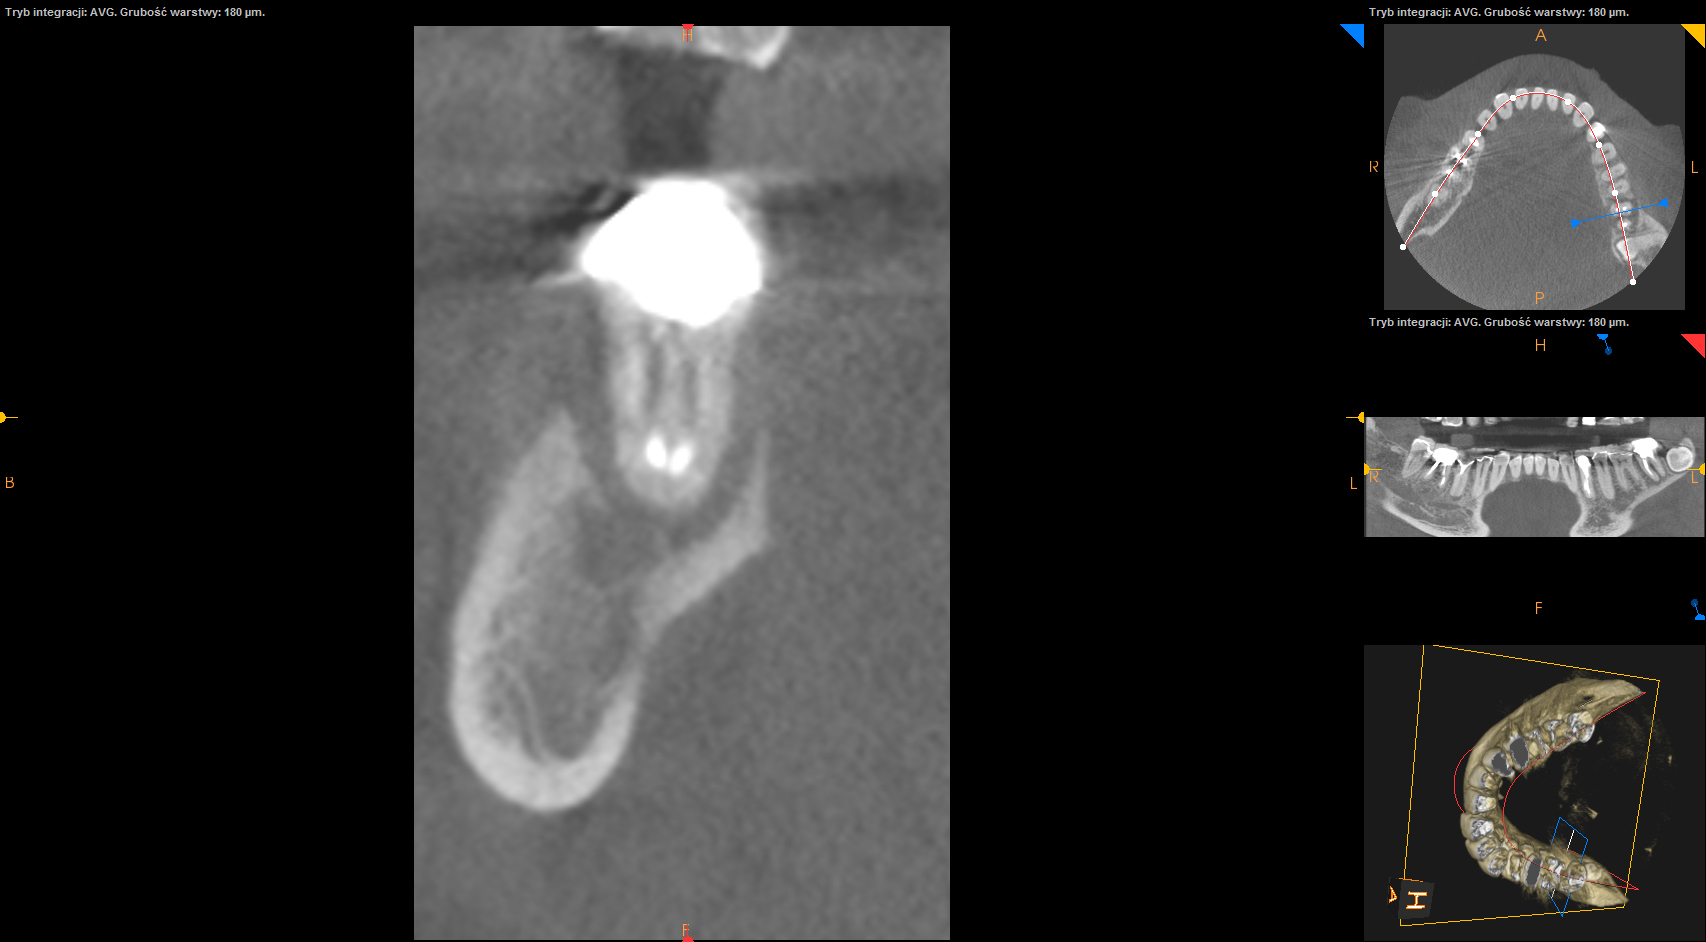

Ten problem najczęściej dotyczy zębów trzonowych żuchwy oraz górnych przedtrzonowców. Może również towarzyszyć wadom zgryzu, w zębach zniszczonych przez erozję, abrazję lub atrycję. Pionowe złamanie korzenia jest trudne do zdiagnozowania. Zdjęcia RTG nie zawsze bowiem ukaże „całą prawdę”. Coraz powszechniej używane obrazowanie CBCT (3D) pomaga w postawieniu diagnozy pionowego złamania zęba lub korzenia.

Do pionowego złamania korzenia zęba może dojść podczas zabiegu leczenia kanałowego poprzez używanie zbyt dużej siły w czasie wypełniania lub oczyszczania kanału. Może być również spowodowane zaklinowaniem się narzędzia w kanale. Pionowe korzenia zęba zawsze prowadzi do usunięcia całego zęba. Dbałość o profilaktykę i terminowe zgłaszania się do gabinetu stomatologicznego z towarzyszącą diagnostyką rentgenowską znaczącą redukuje te ryzyka.

Grupa V – pionowe pęknięcie zęba – pęknięcie korzenia.